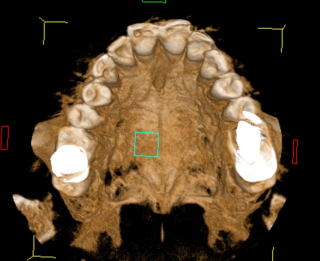

である。開業当初から当診療システムで38年間口腔管理をしている。Panorama、CTなどレントゲンを介しての顎骨・歯槽骨の形態・骨

量などを観察したもので、歯槽骨の吸収状態から診ても、ほぼ二十歳代に相当するように思われる。過去の論文を見ても、口腔内写真

■Volume Rendering(CT)

(図15)2015年7月27日、83歳。高年齢と残存歯数ばかりが問題視されているが、歯槽骨の状態、歯肉、Pocketの状態を含めた歯周病を評価すべきである

歯周病治療38年経過:83歳(女性)残存歯数28本